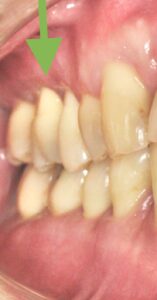

クリーニング希望で来院された患者さんです。

ほとんどの歯に歯石が沈着しているのがわかります。

前歯では歯石付近の歯ぐきの腫れが顕著です。

このように、歯ぐきに炎症を引き起こしていると、歯磨きの時に出血がみられます。